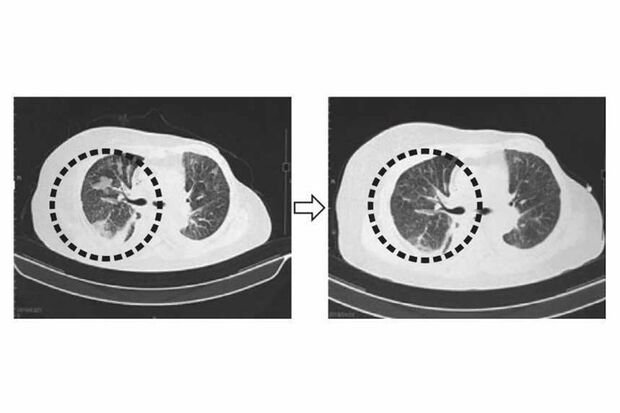

NKT細胞標的治療の流れ

[写真 3/4枚目] NKT細胞標的治療の流れ